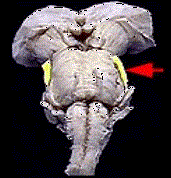

问题 如图箭头所示为哪支脑神经 ( )

选项 A、Ⅱ B、Ⅲ C、Ⅰ D、Ⅴ E、Ⅳ

答案 D